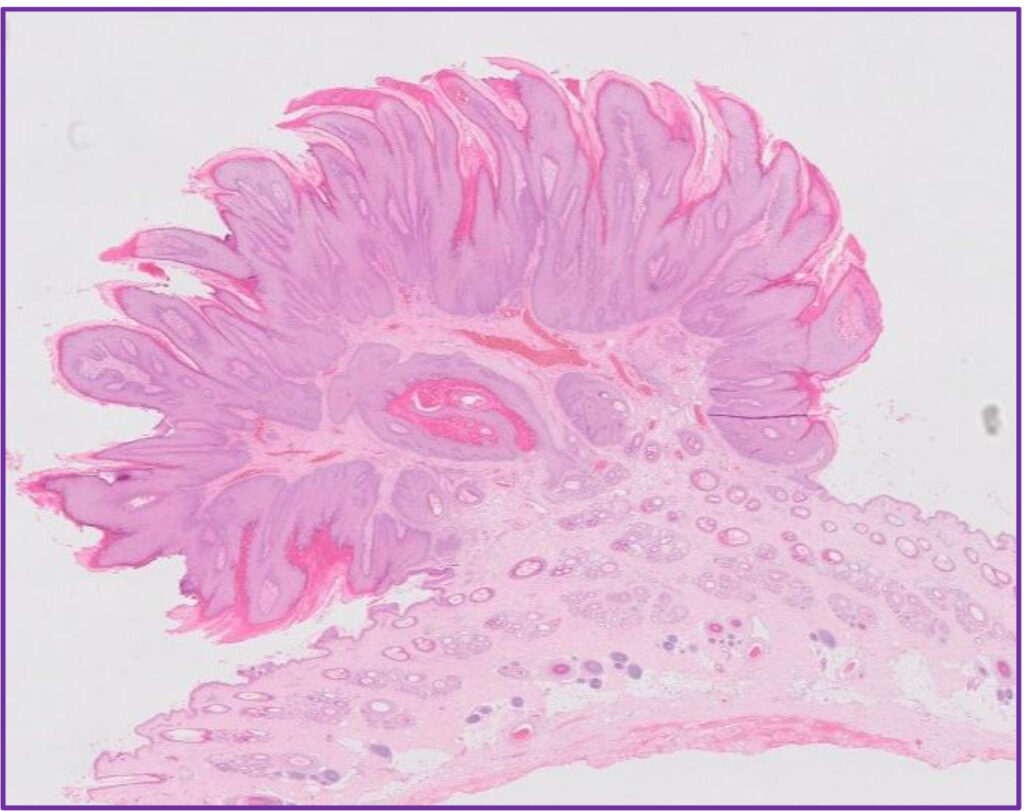

Fig 3. Canine viral papilloma.